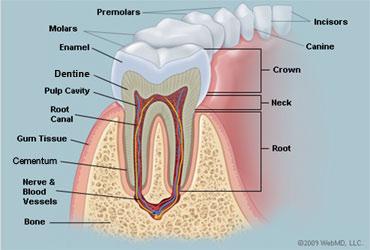

10

11

12

13

baby teeth

Permanent Teeth

Incisors (8)

16

Permanent Teeth

Premolars (8)

18

Permanent Teeth

Crown

Neck

Root

Alveoli

Gingiva

Enamel

Dentin

Cementum